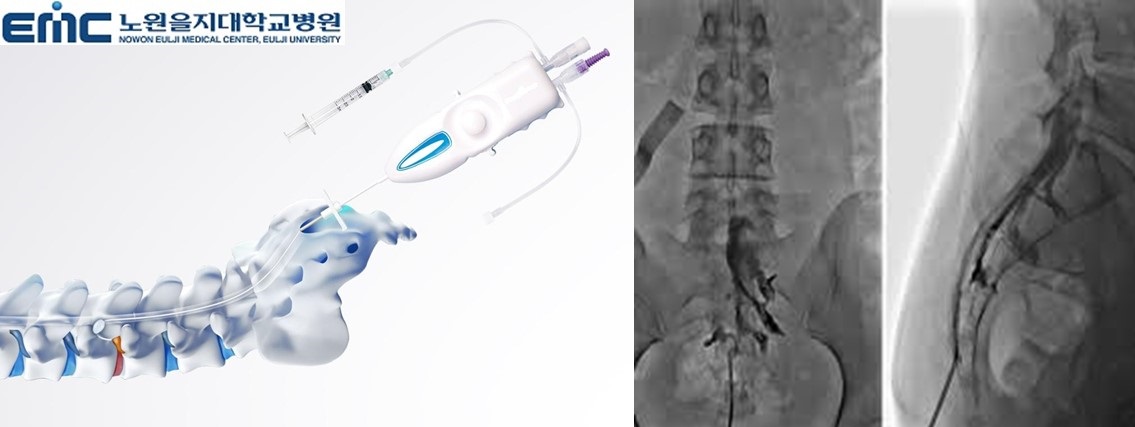

1. 신경성형술

디스크 탈출로 진단된 경우 꼬리뼈의 천추열공을 통해 특수 카테터를 통해 직경이 가느다란 특수카테터를 삽입하여

디스크가 압박하고 있는 신경 주위에 공간을 만들고 직접 약물을 투입하는 시술입니다.

2. 풍선확장술

척추관 협착증으로 진단된 경우 꼬리뼈의 천추열공을 통해 특수 카테터를 병변 부위에 위치시킨 다음 카테터 끝에

있는 풍선을 부풀려 척추관의 공간을 넓혀주고 약물을 직접 병변에 주입하는 시술입니다. 통증이나 전신마취

필요성, 흉터, 출혈이 없으며 시술시 피부를 최소한으로 절개하여

풍선이 내장된 특수 카테터를 삽입하고 풍선을 부풀림으로써 좁아진 척추관을 넓히는 시술입니다.